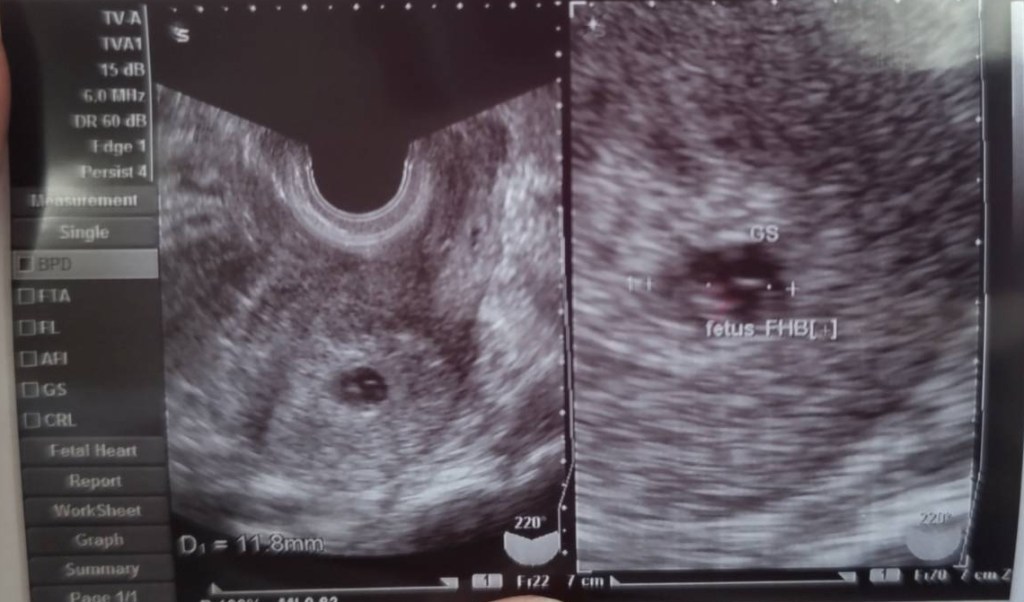

この度妻が新しい命を授かりしました👩🍼

約6週になります、安定期までは油断できませんが見守りたいと思います😊